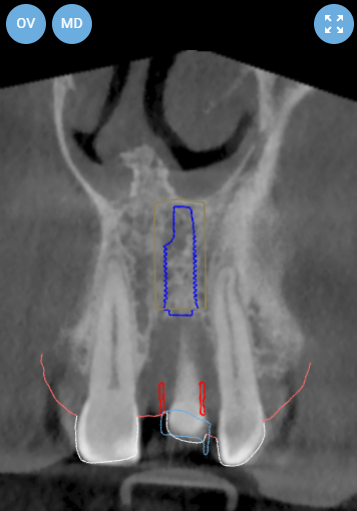

Pre-operative planning was performed using the DICOMLAB digital planning platform. The workflow included a pre-operative CBCT scan of the upper jaw and a digitalintraoral scan.

These datasets were merged within the DICOMLAB software to allow prosthetically driven implant planning.

Planned implant:

DSI Conical Implant - 4.3 mm diameter, 13 mm length.

A custom surgical guide was fabricated using the DICOMLAB open platform, which allows surgical guide production for most implant systems.